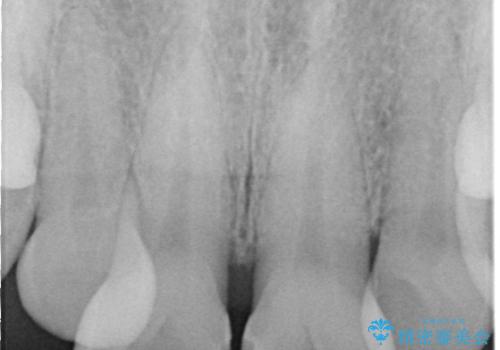

- 前歯の隙間とへこみが気になり、特に舌で触ると気になってストレスを感じるとのことで来院された患者様です。

上下ともに軽度の叢生があり、下顎がやや前突傾向にあったため、本来であれば矯正治療が第一選択となります。矯正によって下の前歯を後方に移動させることで、咬み合わせの改善とともに前歯のデコボコも整えることができます。

上下に叢生(歯のデコボコ)と反対咬合があるため、本来であれば矯正治療が最も理想的な治療選択となります。